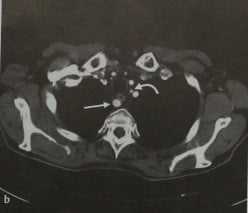

На снимках ниже представлен больной с уровнем стеноза

1) на правой около 50%

2) на левой больше 80%

КТ после введения контрастного вещества. Поперечная (а, b) и косая (с) MIP проекции правой подключичной артерии (стрелка). На рисунке представлен вариант отхождения левой позвоночной артерии (b, искривленная стрелка) напрямую от дуги аорты. При этом она визуализируется между левой общей сонной и левой подключичной артериями